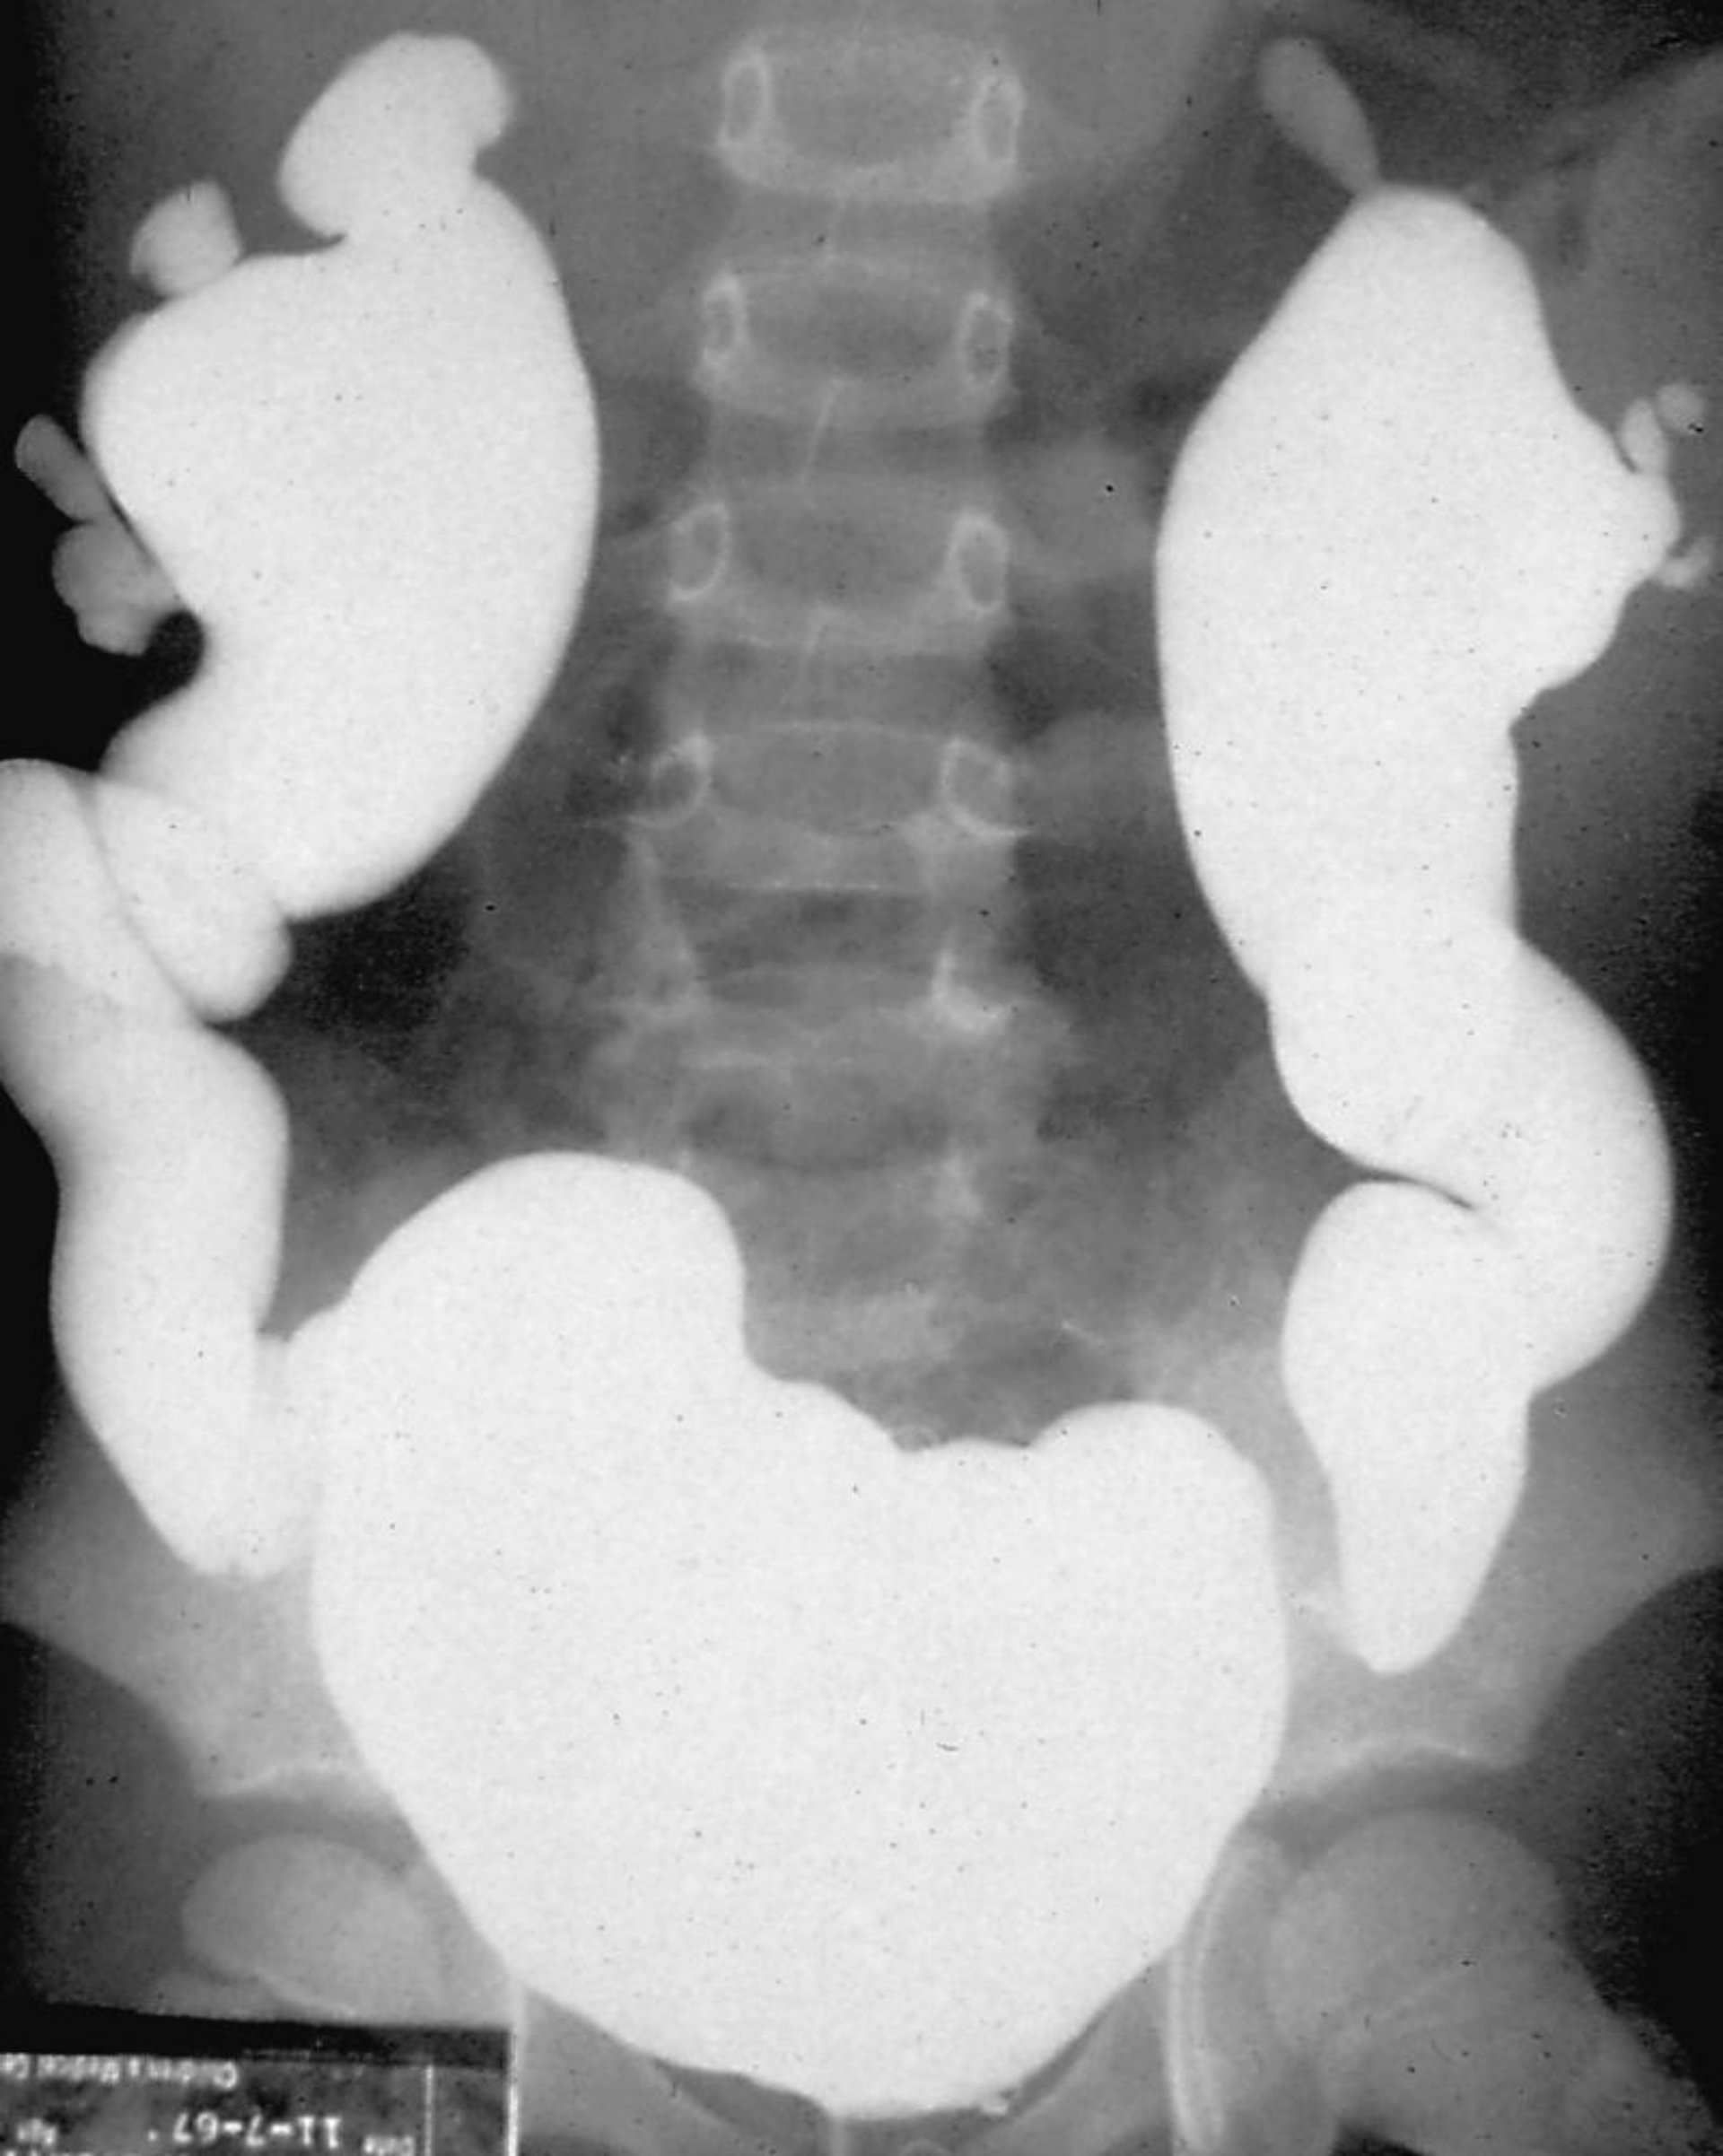

Nefropatía por reflujo (cistouretrografía miccional)

La cistouretrografía miccional se realiza llenando la vejiga con material de contraste radiológico y observando el reflujo bajo fluoroscopia, ya sea durante la fase de llenado de la vejiga o durante la micción.